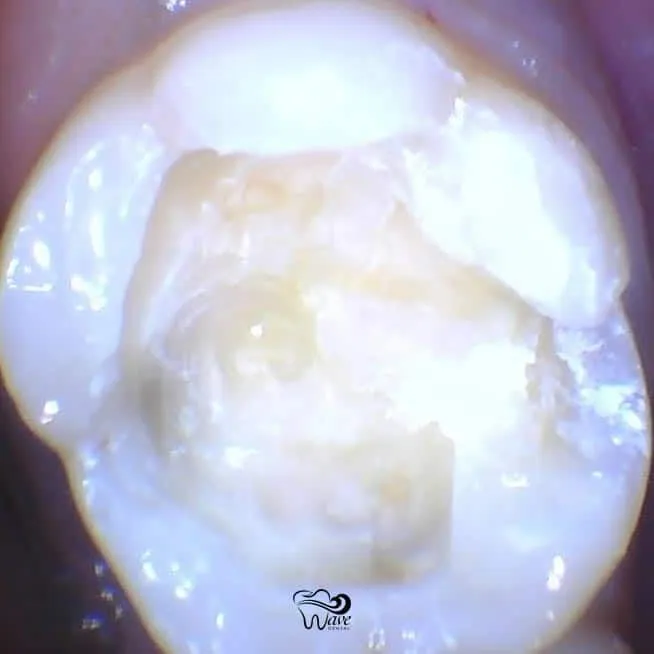

While fillings can occasionally break, fall out, or cause you pain, the signs of a failing restoration are usually not so obvious. Once the “margins” or edges of a filling have broken down and allowed leakage of bacteria, recurrent decay can creep underneath and grow undetected until it leads to an infection of the nerve tissue.

In other cases, a crack can form on the edge of a tooth after years of chewing forces. Again, decay can form in this gap, or worse, the entire tooth could fracture, sometimes leading to loss of the tooth.

In most cases, an old filling is simply removed, along with any recurrent decay, and replaced with a new filling. Depending on how deep the original filling is, and how much damage has been caused by decay and fractures, some teeth may also require a root canal or a crown.